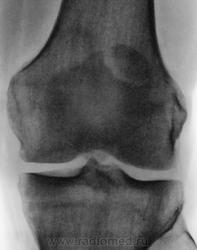

Травма. Направлен на рентгенографию коленного сустава

Несросшийся апофиз надколенника, деструкции не вижу

Без костных травматических изменений.

Такое развитие надколенника. Хотя может быть и травматический разрыв фиброзных сращений.

Подумала и решила исправить запись -исход остеохондропатии надколенника

А, может быть просто пателла бипарцита?

Можно уточнение ? Край основной массы надколенника неровный, углы заострены и щель выглядит неравномерной -это обычная картина при удвоении надколенника ?

И мне это не понравилось. И по боковой - впечатление о смещении фрагмента.

Мужчина 39 лет, жалоб нет. Обратил внимание на разницу с другим коленным суставом (выпирает). Второй сустав на снимке без изменений. Травм утверждает, что не было.

Получается просто удвоение наколенника ....не попадалось